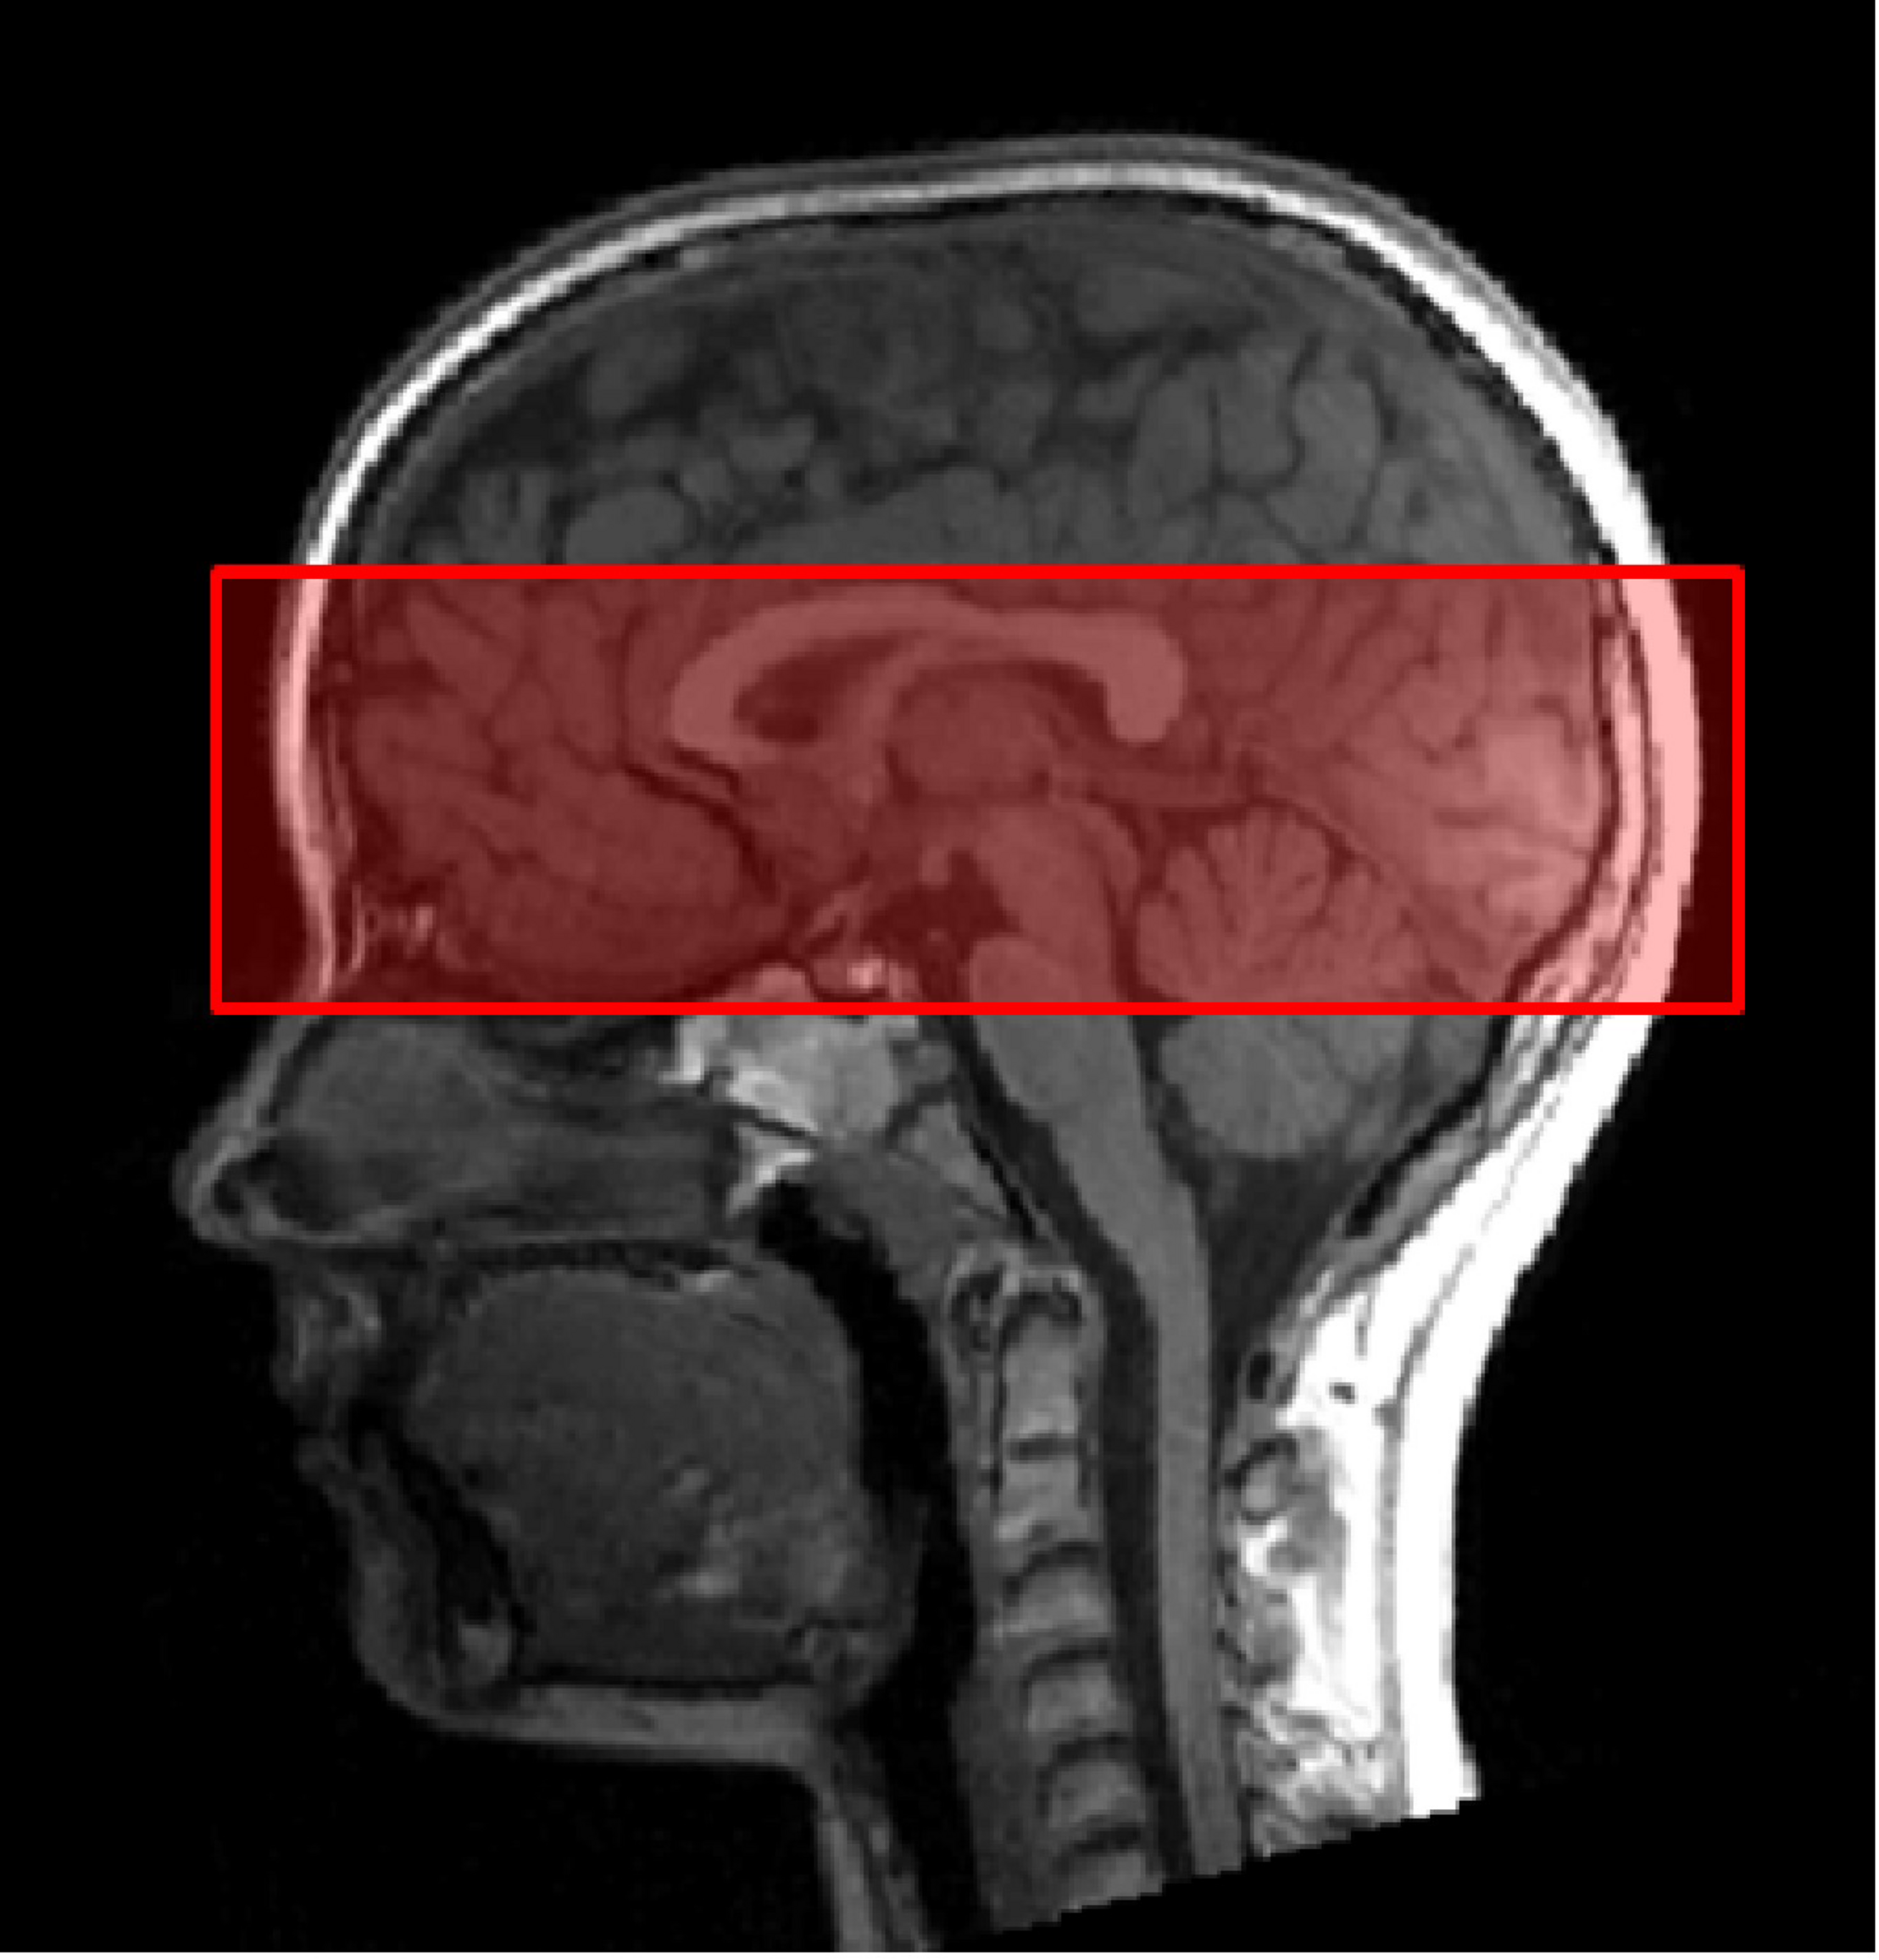

Second, functional images were collected using a T2∗-weighted gradient echo-planar imaging (EPI) sequence sensitive to Blood Oxygen Level Dependent (BOLD) contrast. The following parameters were used: TA 11:14 min, TR 1780 ms, TE 36 ms, FOV 256 mm, 20 slices per slab, ST 2.4 mm, resolution 2.0 × 2.0 × 2.4 mm, PE anterior ≫ posterior, DF 20%, flip angle 70°, bandwidth 1396 Hz/Px, ascending acquisition. We did not measure the whole brain, but only a slab (Figure 2). Reducing the coverage allows reduction of the voxel size and therefore an increased spatial resolution. The measurement of a slab of the brain is believed to facilitate the measurement of small regions (e.g., amygdalae; Morawetz et al., 2008). The slab was manually orientated, using the structural T1-weighted image. We aimed to cover on the one hand all three regions of the core face processing network, i.e., bilateral OFA, FFA, and pSTS. On the other hand, we also aimed, as part of a related project, to measure activity in parts of the extended system, in particular the amygdala, insula, cingulate gyrus, and inferior frontal gyrus. These brain regions are known to play an essential role in emotion processing across development.

FIGURE 2

Slab orientation covering bilateral OFA, FFA, and pSTS. The slab was oriented at the lowest part of the occipital pole and the lowest part of the prefrontal cortex (PFC), using the middle view of the structural image.